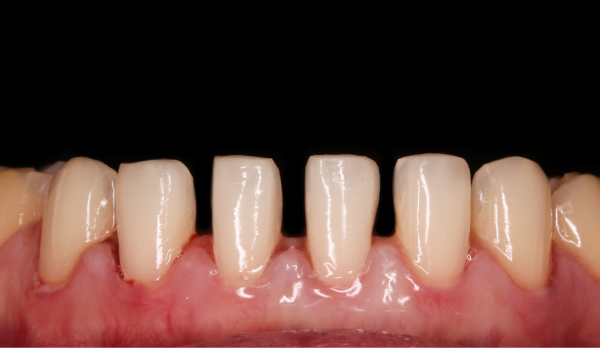

위 영상 자료는 미니쉬치과병원에서 미니쉬를 진행한 초상권 환자입니다

03.미니쉬 치료

04.미니쉬 치료